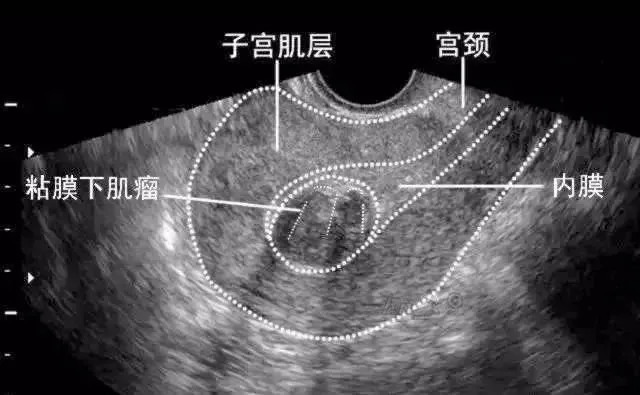

黏膜下肌瘤

经阴道超声扫查表现为子宫内膜变形或缺损,内膜下肌层可见低回声结节突向宫腔,带蒂的粘膜下肌瘤可以突入宫颈管内,形成宫颈管内实性占位声像,仔细扫查可见其与子宫壁有蒂相连,有时呈多发性粘膜下肌瘤。